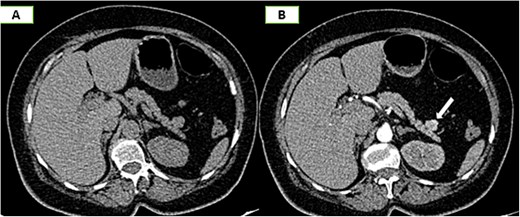

On the complementary CT scan, this lesion exhibits the same tissue characteristics and enhancement as the spleen (Fig. 2), along with its own vascularization through a distinct vascular pedicle (Fig. 3), which is more suggestive ‘of an accessory spleen than an insulinoma of the tail of the pancreas.’

Axial sections of an abdominal non-contrast CT scan (A) and in the arterial phase (B) reveal a nodule adjacent to the tail of the pancreas that is hypervascular on arterial phase and follows the same pattern of enhancement as the spleen.